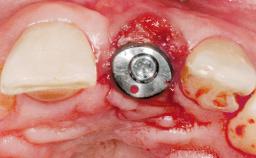

Immediate Flapless Placement of an Implant in a Maxillary Left Central Incisor Site

Placement Protocol Immediate implant placement

Tooth Site Maxillary incisor or canine

Socket Morphology Single-root socket

Socket Integrity Damage to one or more bone walls

Bone Volume Damage to one or more socket walls

Type of Implants One-Piece